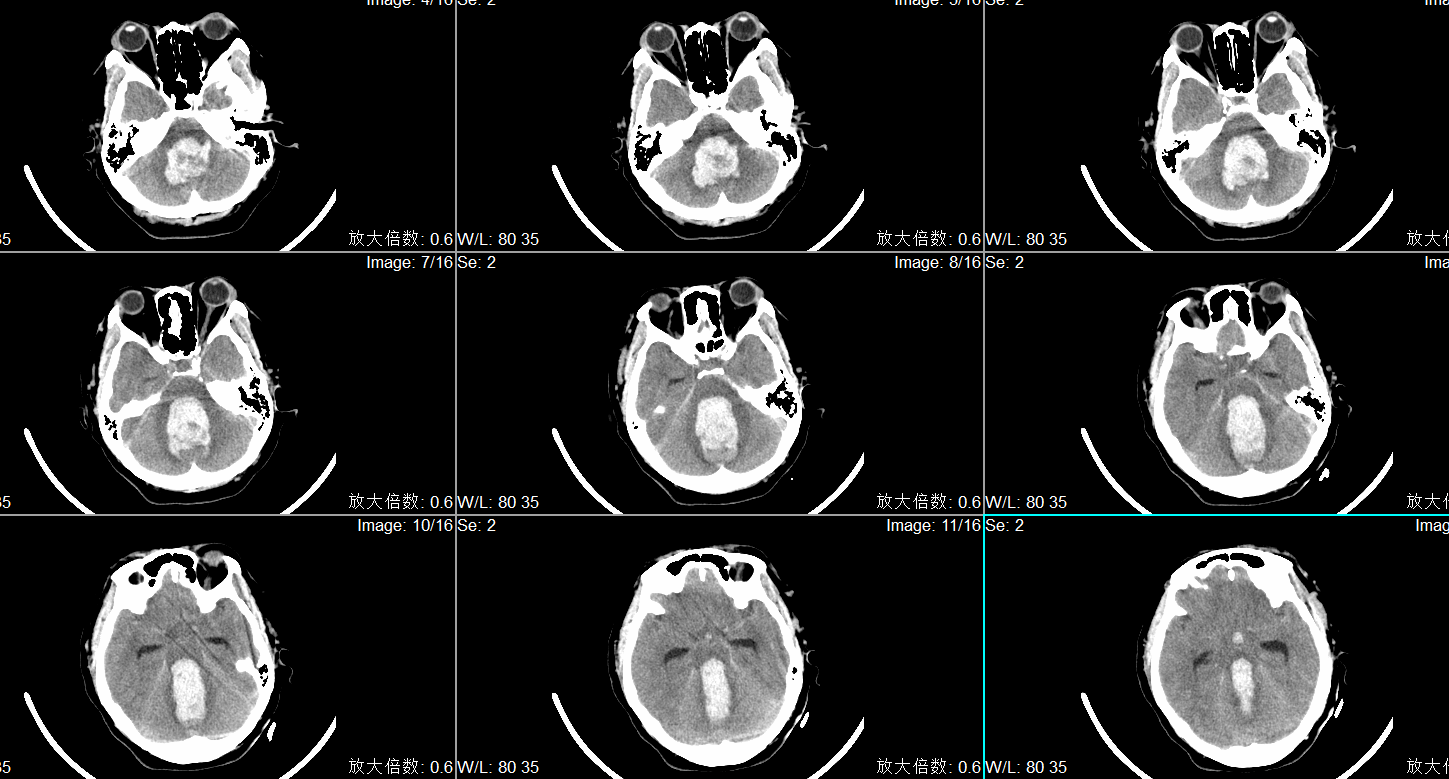

入院头CT显示小脑蚓部出血破入第四脑室、第三脑室及第四脑室。

入院诊断为:1.小脑蚓部出血 2.高血压病3级(极高危)3.吸入性肺炎。

术前头CT